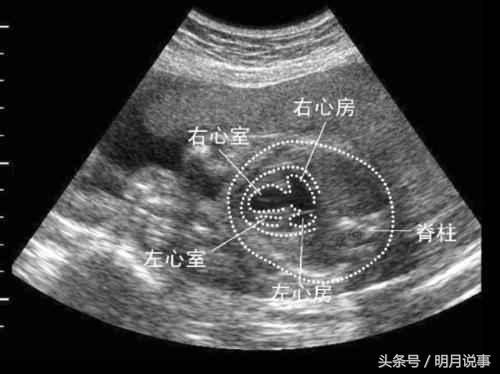

做第二次检查时,小陆是拖着软绵绵的进去的,流泪满面出来的。检查结果和第一次一模一样,胎儿心脏严重畸形,左心发育不良,永存动脉干。